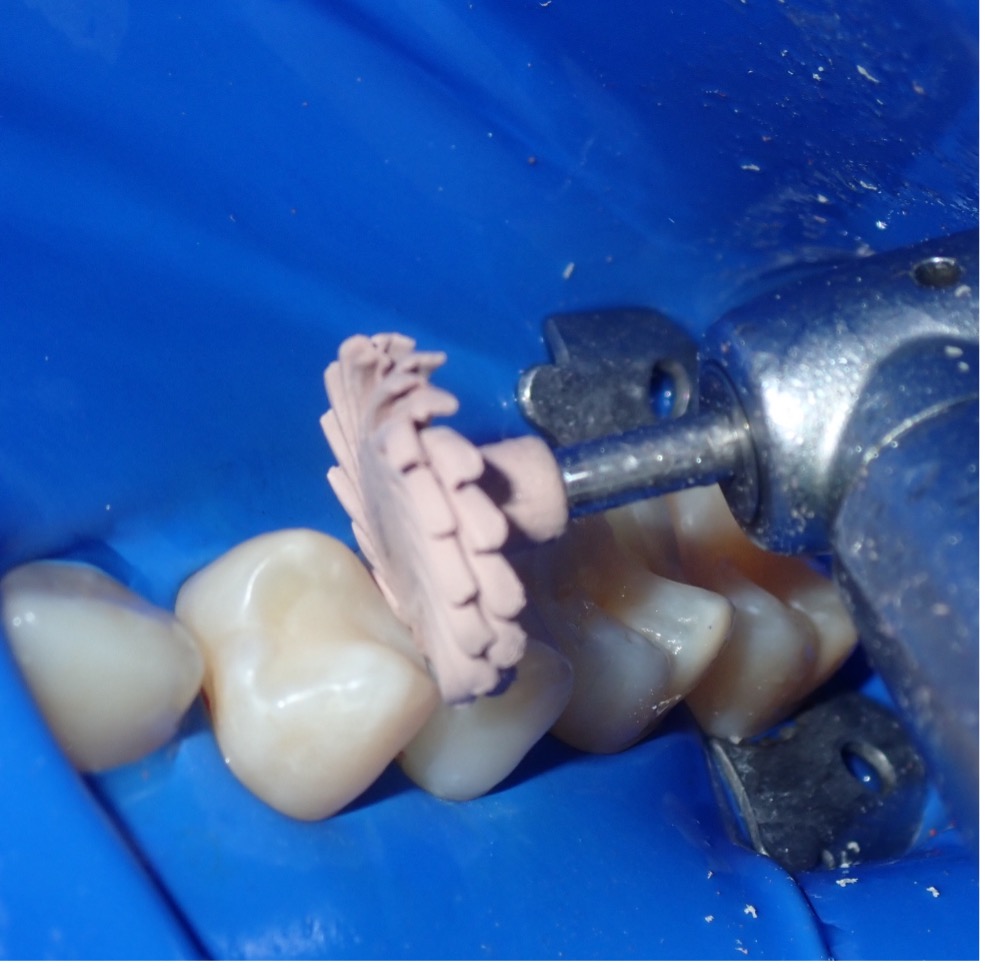

In this case, both teeth were prepped, and the Quad System was placed to ensure stable contact creation during the restoration process. Anatomically shaped wedges and separating rings were inserted to achieve optimal band adaptation and gingival seal (Fig. 5 & 6).

Figure 5-6. Simultaneous placement facilitates the restoration of back-to-back Class II lesions with proper contact and contour.